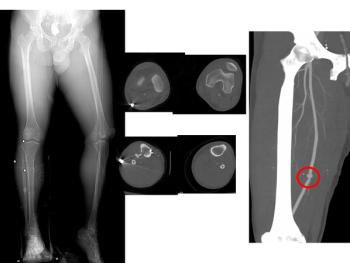

Findings of a study released Sunday at the 2009 RSNA meeting by researchers in Boston suggest CT angiography could help radiologists identify the factors that keep some types of lower extremity fractures from healing faster and better than other, similar lesions.